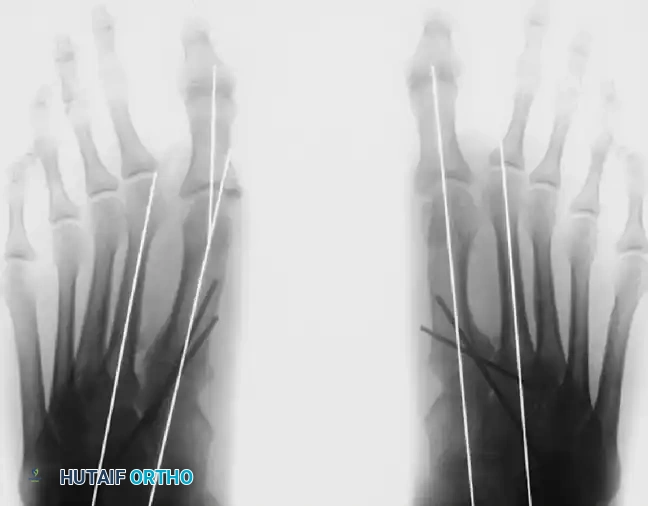

Preoperative radiograph of the same patient. Note the congenital shortening of the second metatarsal, which alters forefoot biomechanics and load distribution.

Postoperative radiograph demonstrating excellent alignment following a distal chevron osteotomy combined with an adductor release.